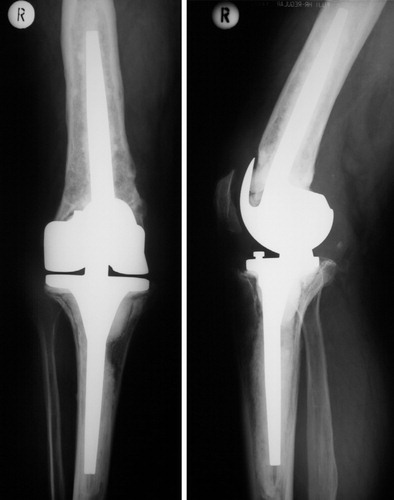

Understanding Hip Implant Components in Revision Surgery

A total hip replacement consists of several components that may fail over time. In revision hip replacement surgery in Surat, Dr. Krunal Donda evaluates which components require replacement: the acetabular cup (socket), femoral stem, femoral head (ball), and polyethylene liner.

Understanding component failure is crucial for successful revision hip surgery. Some revisions involve only the acetabular side, others only the femoral side, while complex cases require complete revision of all components with extensive bone reconstruction. Dr. Donda's expertise in complex hip revision surgery ensures optimal component selection and surgical technique for each patient at Shivaan Hospital.